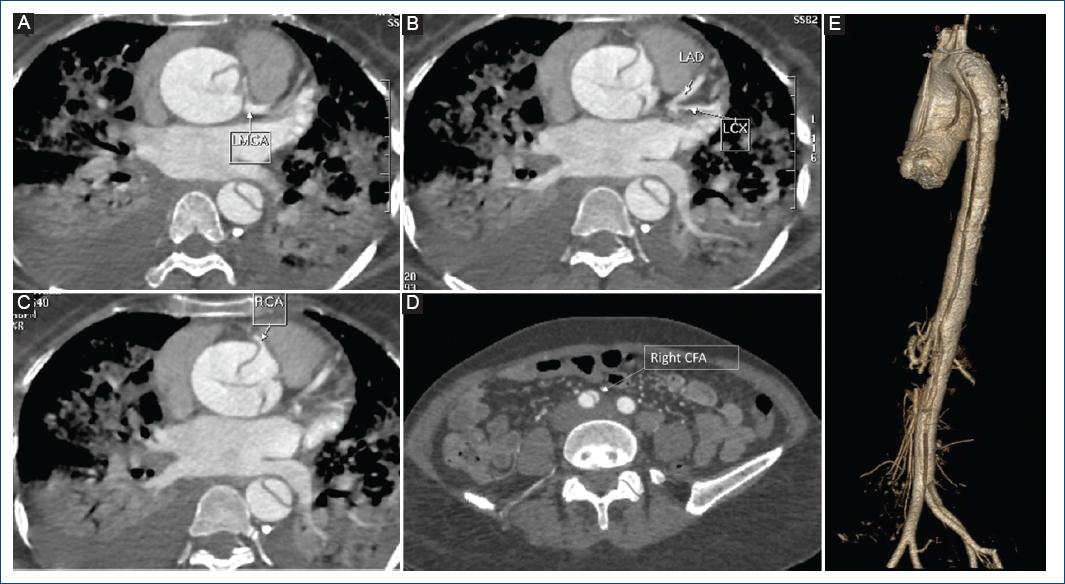

A middle-aged woman with no comorbidities presented to the emergency department with chest discomfort and breathlessness. Vitals showed tachycardia, hypotension, and a soft early diastolic murmur, and a chest X-ray revealed acute pulmonary edema. Twelve lead electrocardiogram (Fig. 1A) showed sinus rhythm with ST depression in 2, 3, aVF, V3-V6, ST elevation in aVR, and lead 1 suggestive of an acute coronary syndrome involving the left main coronary artery. A transthoracic echocardiogram showed severe left ventricular dysfunction, global LV hypokinesia, and a tricuspid aortic valve with an oscillating flap-like structure was observed in the ascending aorta; indicating an acute aortic dissection (Fig. 1B-F). The patient was shifted for emergency surgery after computed tomography-Aortography, which confirmed the diagnosis of De-Bakey Type I dissection with a curvilinear dissection flap extending from the ascending aorta, involving the arch of aorta up to the right common femoral artery (Fig. 2D and E). The dissection flap is seen occluding the Left main with hypoperfusion in the left anterior descending and left circumflex (Fig. 2A and B), with the right coronary artery being spared (Fig. 2C). Despite the surgery, the patient did not survive in the post-operative period.

Figure 2 A-D: multidetector computed tomography (CT) aortogram demonstrating aortic dissection flap arising from ascending aorta, occluding the left main coronary artery and extending till the right common femoral artery. E: 3D reconstruction of the CT aortogram showing the dissection flap involving the whole length of the aorta and its extension into the right common femoral artery.